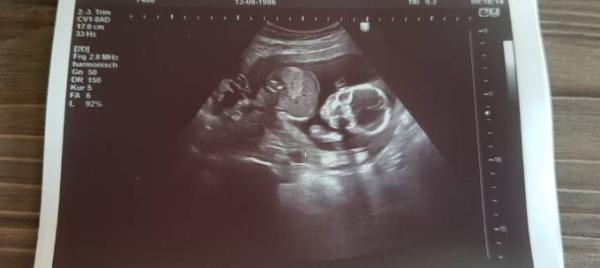

und 2. Bildchen....zwischen die Beinchen

Bild zu

Das sind ja tolle Neuigkeiten:) Das Bild sieht eindeutig nach Mädchen aus :) Wir waren gestern auch zur Kontrolle und das Outing Blau hat sich bestätigt Nächste Woche ist hier bei uns babybörse. Bis dahin muss ich die Klamotten der Großen mal aussortieren, damit schauen kann, was ich brauche

Ja Sie meinte auch eindeutig Mädel. Ach schön da habt ihr dann ein Töchterchen und ein Söhnchen @ Juilette-Baguette